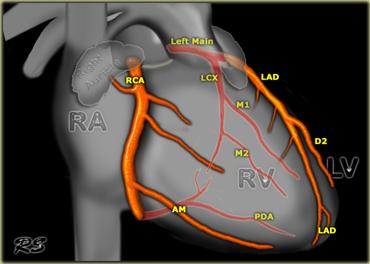

Bên trái là hình tổng quan các động mạch vành trên tư thế chiếu thẳng trước.

- Thân chung động mạch vành trái hay động mạch vành trái (LCA)

Động mạch liên thất trước (LAD)

- Các nhánh chéo (D1, D2)

- Các nhánh vách

Động mạch mũ (Cx)

- Các nhánh bờ (M1, M2)

Động mạch vành phải

- Nhánh bờ cấp (AM)

- Nhánh nút nhĩ thất

- Động mạch liên thất sau (PDA)